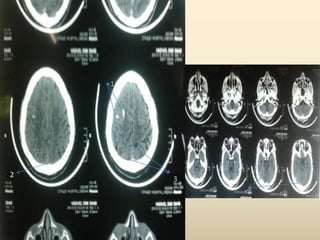

CT-BRAIN REPORT

 CT BRAIN AXIAL SECTIONS SHOWING

1. HYPERDENSITY IN THE RIGHT FRONTAL

REGION

2. HYPERDENSITY IN THE R TRANSVERSE

SINUS

3. HYPODENSITY IN THE SUPERIOR SAGITTAL

SINUS (?EMPTY DELTA SIGN)

 SUGGESTIVE OF ?PARENCHYMAL

HEMORRHAGE WITH CORTICAL VEIN

THROMBOSIS ?CALCIFIED GRANULOMA.

1

22

3